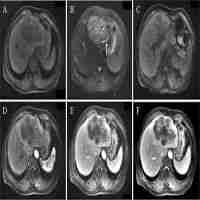

| Abstract | Introduction: Hepatic sarcomatoid carcinoma (HSC) is a rare type of liver cancer with a high malignant grade and poor prognosis. This study compared the clinical characteristics and magnetic resonance imaging (MRI) features of HSCs with those of hepatocellular carcinoma (HCC) and intrahepatic cholangiocarcinoma (ICC), aiming to identify valuable features for HSC diagnosis. Methods: In total, 17 pathologically confirmed HSC cases, 50 HCC cases and 50 common ICC cases were enrolled from two hospitals. The clinical characteristics and MRI features of all cases were summarized and statistically analyzed. Results: On the one hand, the incidence rates of elevated carbohydrate antigen (CA) 19-9 and elevated carcinoembryonic antigen (CEA) were significantly higher in the HSC cases than in the HCC cases (29.4% vs. 0%; 17.6% vs. 0%). The HSC enhancement patterns, primarily including progressive enhancement, were also significantly different from HCC cases. The incidence rates of heterogeneous signals on T2-weighted imaging and during the arterial phase were significantly higher in the HSC cases than in the HCC cases (94.1% vs. 66.0%; 100.0% vs. 72.0%). The diameter of HSCs was significantly larger than that in the HCC cases (6.12 cm vs. 4.21 cm), and the incidence rates of adjacent cholangiectasis, intrahepatic metastasis and lymph node enlargement were considerably higher in the HSC cases than in the HCC cases (52.9% vs. 6.0%; 47.1% vs. 12.0%; 41.2% vs. 2.0%). On the other hand, the incidence rate of elevated CA199 was significantly lower in the HSC cases than in the ICC cases (29.4% vs. 60.0%). The incidence rates of intratumoral necrosis and pseudocapsules were significantly higher in the HSC cases than in the HCC cases (35.3% vs. 8.0%; 47.1% vs. 12.0%). However, the incidence rates of target signs were significantly lower in the HSC cases than in the HCC cases (11.8% vs. 42.0%). In addition, there was no significant difference in the enhancement patterns between HSC cases and ICC cases. Conclusions: HSCs were frequently seen in elderly men with clinical symptoms and elevated CA199 levels. The MRI features, including large size, obvious heterogeneity, hemorrhage, progressive enhancement, pseudocapsule and lymph node enlargement, contributed to the diagnosis of HSC. |